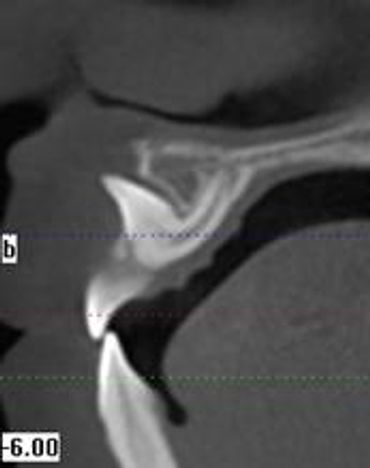

CBCT is a digital x-ray scanner specifically designed for scanning the head and jaws. The scanner rotates 360 degrees around the patient's head in a matter of seconds. The x-ray is a low energy fixed anode tube similarly used in panoramic machines. This method reduces radiation scatter common to most conventional x-rays. The cone shaped x-ray provides 360 views that can be presented in 2D image and 3D volume for advanced planning and diagnostic support.

This one scan provides more images than plain film conventional imaging, with complete visualization of the patient's entire maxillofacial region. These images clearly display TM disorders, impacted teeth, critical bone and tooth relationships, oral- nasal airways, para-nasal sinus, mandibular canal and difficult to see pathologies within one volume. The user friendly software system reconstructs true size, distortion free, high resolution images.

The CBCT scanner is fast, comfortable (nothing goes in the mouth), and painless for patients. It provides a complete set of maxillofacial images with less radiation than conventional orthodontic and medical type CT work-ups. CBCT now can re-create true size cephalometric and panoramic images, virtually eliminating the need for conventional orthodontic x-rays, so your patients will be comforted by the knowledge that you have all the information needed to evaluate and plan their treatment

Voxel: We also can choose the voxel size of the scan. Voxel derives from the terms combine from Pixel and Volume. The best depiction that I can give you is a rubics cube.

The smaller the cube the higher definition of the scan. Our average scan we take is at a .25mm voxel. This allows us to make cross-sectional slicings down to .25 mm, and we typically will measure and print at 1mm. (depending on the study ordered).